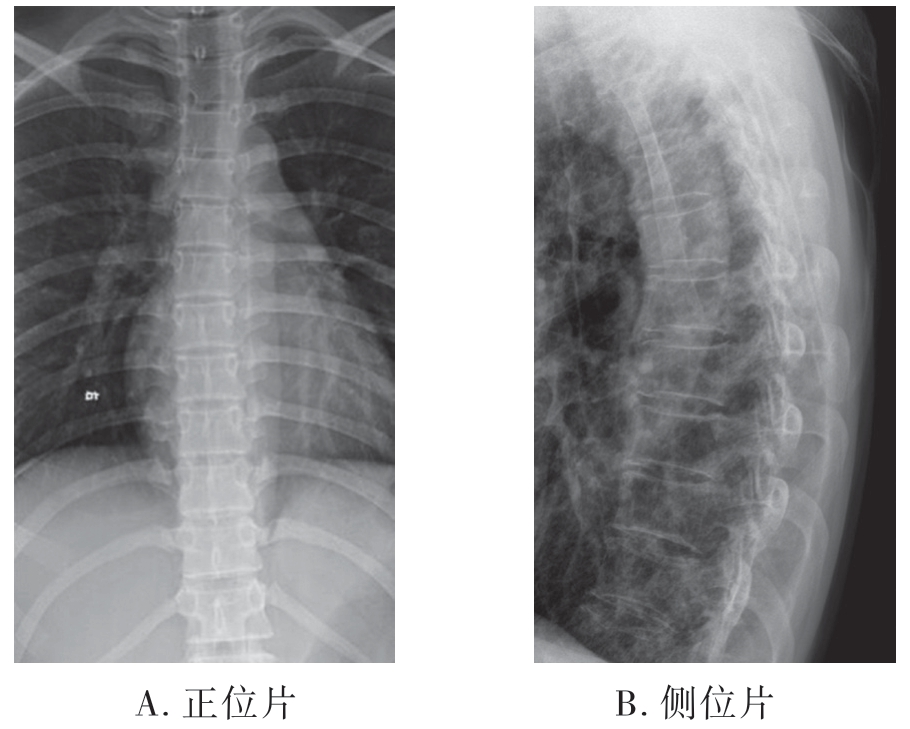

1.X线平片 脊椎受到垂直方向暴力的作用椎体可发生粉碎性骨折。椎体压缩变扁,椎体及附件的骨折片向前后左右各方向移位。X线对爆裂性骨折的显示不如CT检查(图7-2-14)。

图7-2-14 X线平片示腰椎爆裂性骨折